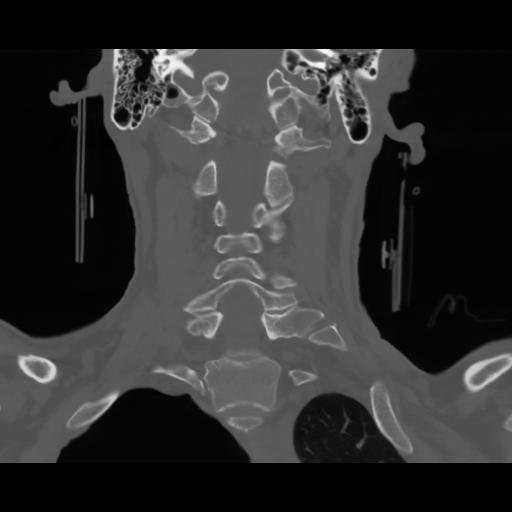

13 P.BLANDAS,,Coronal,2.000,P.BLANDAS,Coronal,